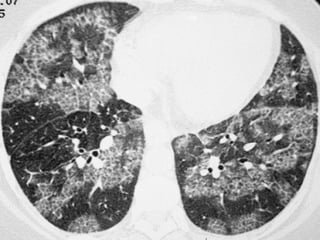

 TCAR  Extensãodo acometimento pulmonar e fase da dça. ▪ Precoce: áreas em vidro fosco ▪ Avançada: faveolamento FIBROSE PULMONAR IDIOPÁTICAFIBROSE PULMONAR IDIOPÁTICA

 Padrão definitivo– Todos os 4 critérios são necessários:  Predominância nas bases e regiões subpleurais;  Anormalidades reticulares;  Faveolamento com ou sem bronquiectasias de tração;  Ausência de todos os 7 critérios inconsistentes com o padrão de UIP FIBROSE PULMONAR IDIOPÁTICAFIBROSE PULMONAR IDIOPÁTICA

FIBROSE PULMONAR IDIOPÁTICAFIBROSEPULMONAR IDIOPÁTICA Fonte: http://www.scielo.br/scielo